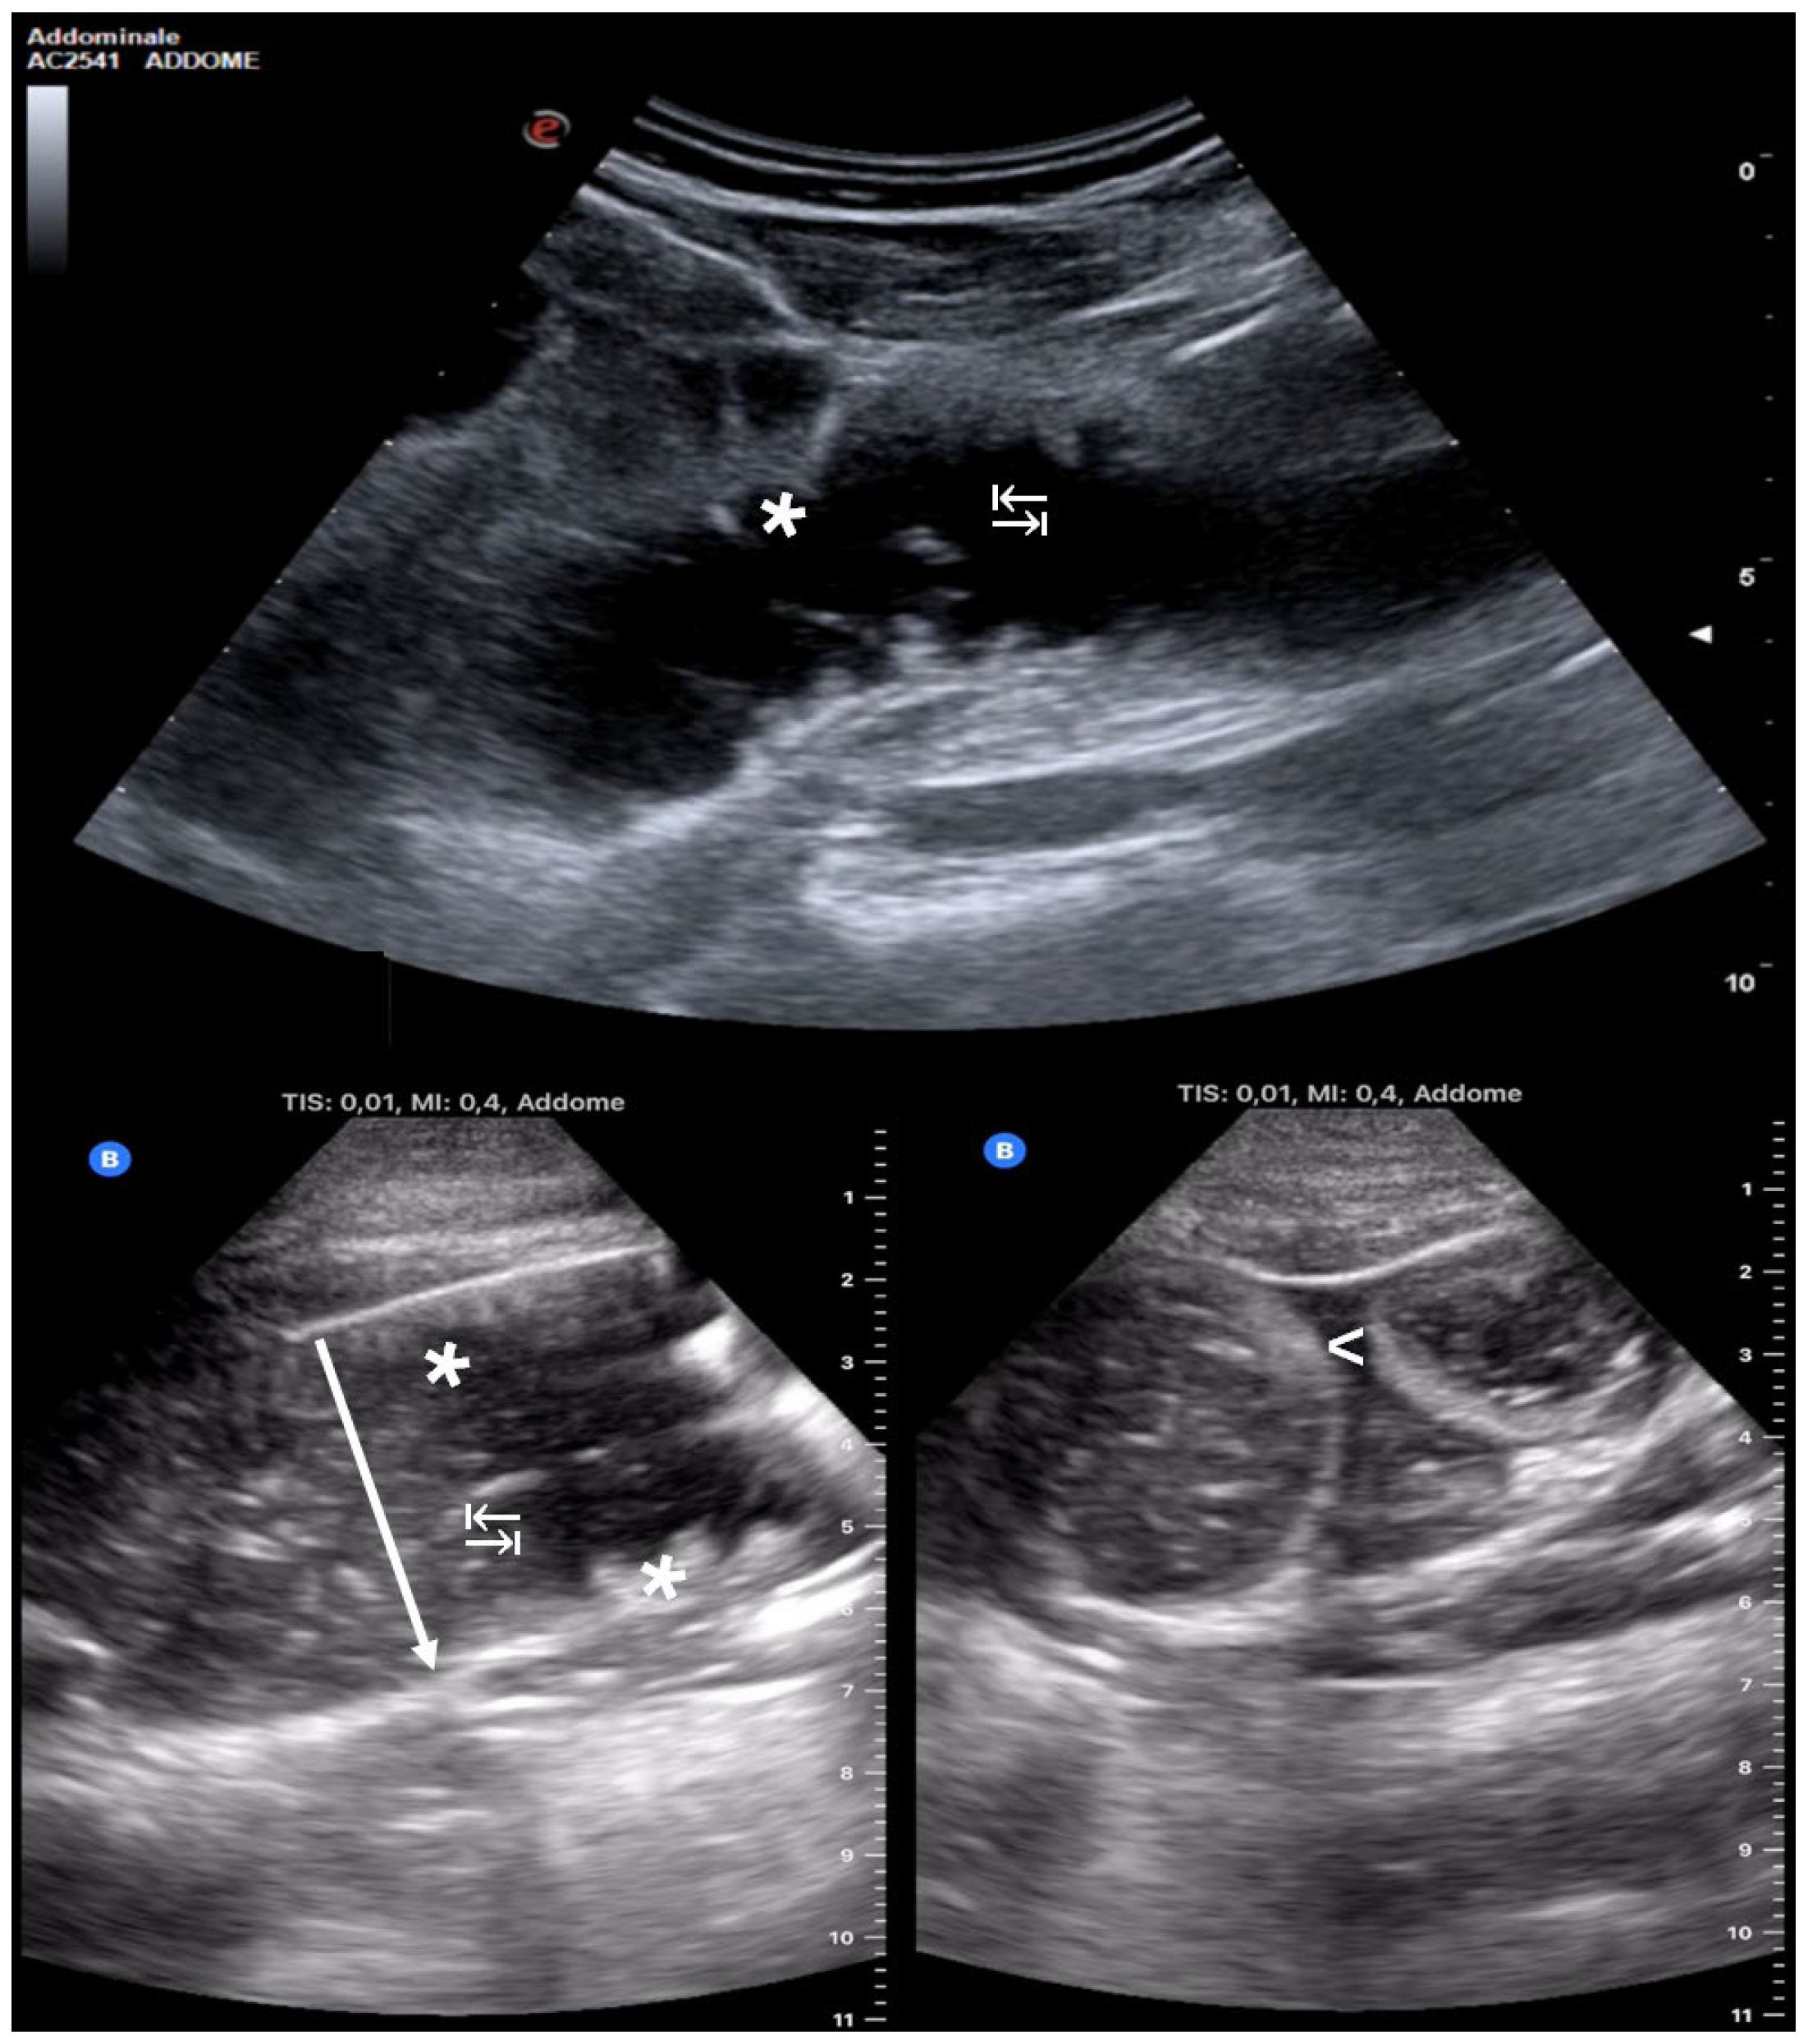

Using the standardized POCUS protocol, providers systematically examined the intestinal loops, starting from the right lower quadrant and following the path of the colon. The starting point was on the terminal ileum in the right lower quadrant. Then, we moved on to the cecum, ascending colon, transverse colon, descending colon, sigmoid colon, and finally the rectum. Subsequently, the small intestine in the upper quadrants and flanks was examined, using longitudinal and transverse imaging planes, in accordance with the American Gastroenterological Association guidelines and expert recommendations on intestinal ultrasound [12]. The diagnosis of SBO through POCUS relied on identifying at least three out of the four ultrasound indicators that are commonly linked to the highest specificity and sensitivity in diagnosing SBO via POCUS: (1) intestinal loops > 2.5 cm in diameter; (2) presence of free fluid between the loops (known as “tanga sign”); (3) observed alternating peristalsis (“to-and-fro” movement); and (4) visualization of circular folds extending perpendicular to the wall of the duodenum and jejunum (referred to as “keyboard sign”) [4] (Figure 1).

Figure 1. The ultrasound images depict four key diagnostic indicators of SBO. Distended intestinal loops (↓) in the figure lower left: with a diameter exceeding the physiological threshold for distension, set at 2.5 cm; the “tanga sign” (<): presence of fluid between the bowel loops with a characteristic triangular “thong-shaped” distribution; the “keyboard sign” (*): hypertrophy of Kerckring folds, typically visible in the jejunum (more numerous) and ileum (less numerous) due to the pathophysiology of SBO; and the “to-and-fro sign” (↹): alternating peristaltic movement caused by downstream obstruction.